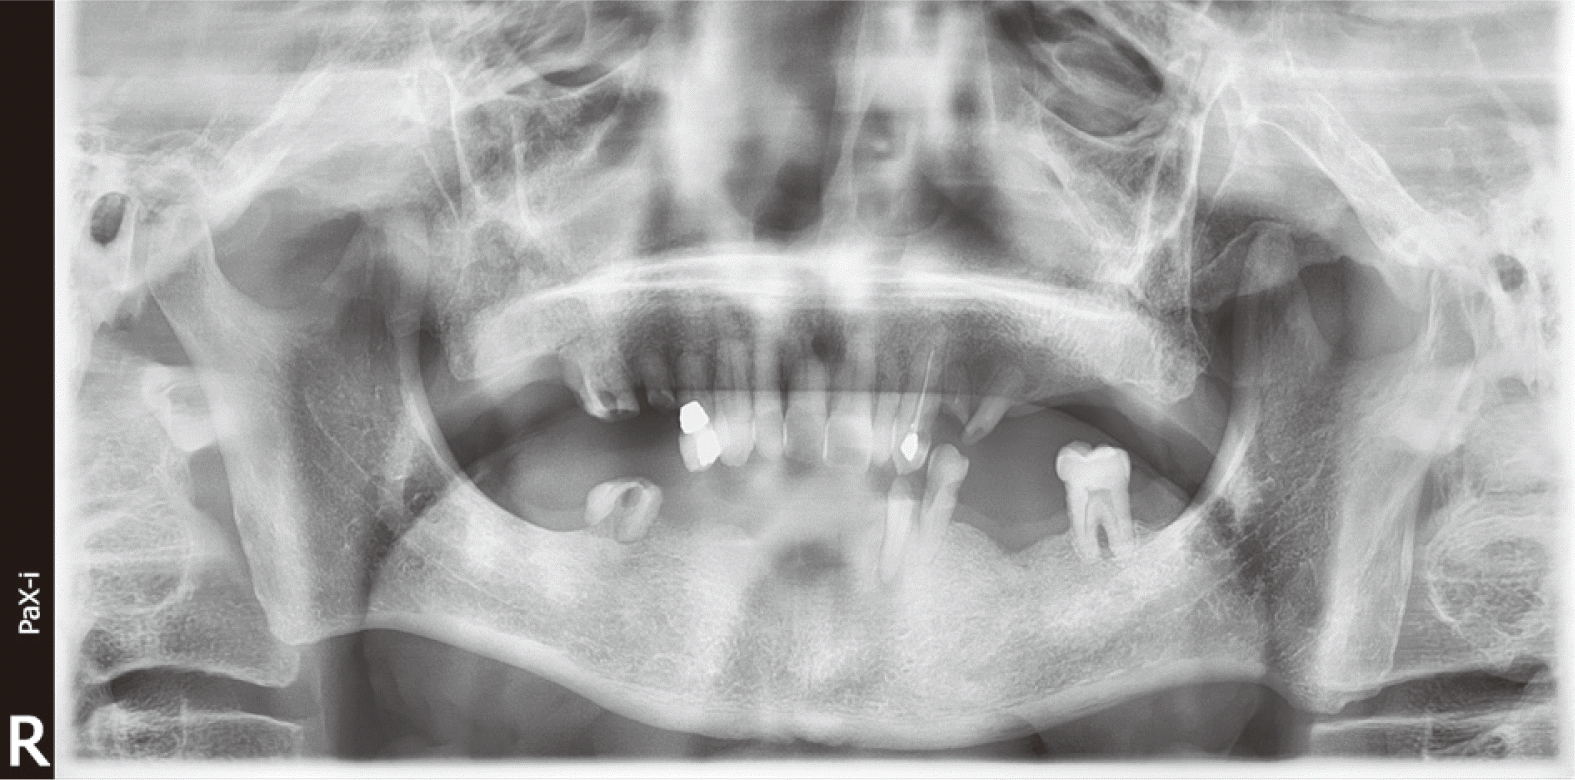

60세 남자 환자로 전체적인 치과치료를 위해 본원에 내원하였다. 환자는 의과적으로 기질성 정신장애를 진단을 받았으며, 거동이 불편하고 보행이 불가능하여 요양병원에서 입원 치료 중이었다. 정신건강의학과에서 환자의 정신장애에 대해 치료상태가 안정된 상태임을 확인한 후, 치과치료를 진행하였다. 파노라마 방사선 사진 및 구강검사에서 상악 우측 제1소구치와 제1대구치, 좌측 제제1, 2소구치, 하악 우측 제1대구치에 잔존 치근이 존재하였으며, 상악 우측 견치와 하악 좌측 견치 및 소구치에서 치아우식증이 관찰되었다(Fig. 1). 환자의 의과적 병력과 치료의 협조도, 구강위생 조절 능력 등을 고려했을 때, 가철성 보철물의 유지와 관리가 어렵다고 판단되어 고정성 보철물로 수복을 계획하였다. 예후가 불량한 상악 우측 견치, 제1소구치, 제1대구치와 좌측 제제1, 2소구치, 하악 좌측 견치, 제1소구치와 우측 1대구치를 발치 한 후, 치아 상실부위에 임플란트 식립을 하였고(Fig. 2), 골유착 기간을 거쳐 최종인상을 채득하였다. 제작한 임플란트 보철물을 장착하던 과정에서 치과의사는 하악 우측 제제1, 2소구치와 제1대구치로 이루어진 3본 지르코니아 보철물이 환자의 구강 내로 떨어뜨렸고, 떨어진 즉시 환자의 두부를 좌측으로 돌려 환자가 보철물을 삼키지 않도록 노력하였으나, 환자가 보철물을 삼키게 되었다. 환자가 보철물을 삼킨 이후 기침이나 구토 반사 등의 특이적 소견을 보이지 않았으며, 호흡상태는 양호하였다. 환자 보호자에게 보철물 장착과정에서 보철물을 구강 내로 떨어뜨렸고, 이후 삼킴이 발생하였음을 설명하였다. 그리고 삼켜진 보철물의 위치 확인을 위하여 인근 내과로 전원 의뢰를 시행하였다. 전원 의뢰된 당일, 내과에서 복부 방사선 사진을 촬영하였고, 판독 결과 보철물이 위장에 위치를 하고 있음을 확인하였다. 24시간 이후 배출될 것으로 예상되어 48시간 후 재촬영이 필요할 것이라는 회신서를 확인하였다(Fig. 3). 2일 후 환자를 내원하도록 하여 추가로 복부 방사선 사진을 촬영하였다. 방사선 사진에서 위장관 내에서 보철물 확인되었다. 환자의 거동이 불편하여 위장관 운동이 저하되어 있는 상태이기 때문에 배출이 지연될 수 있다는 의과적 소견을 회신 받았다(Fig. 4). 8일 후 환자의 복부 방사선 사진을 촬영하였으며, 보철물이 위장관에서 완전히 배출되어 체 내에 있지 않음을 확인하였다(Fig. 5). 이 후 하악 우측 제1, 2소구치와 제1대구치에 새로운 보철물을 제작하여 최종 합착(Rely-X, 3M ESPE, St Paul, USA)을 시행하였다(Fig. 6).